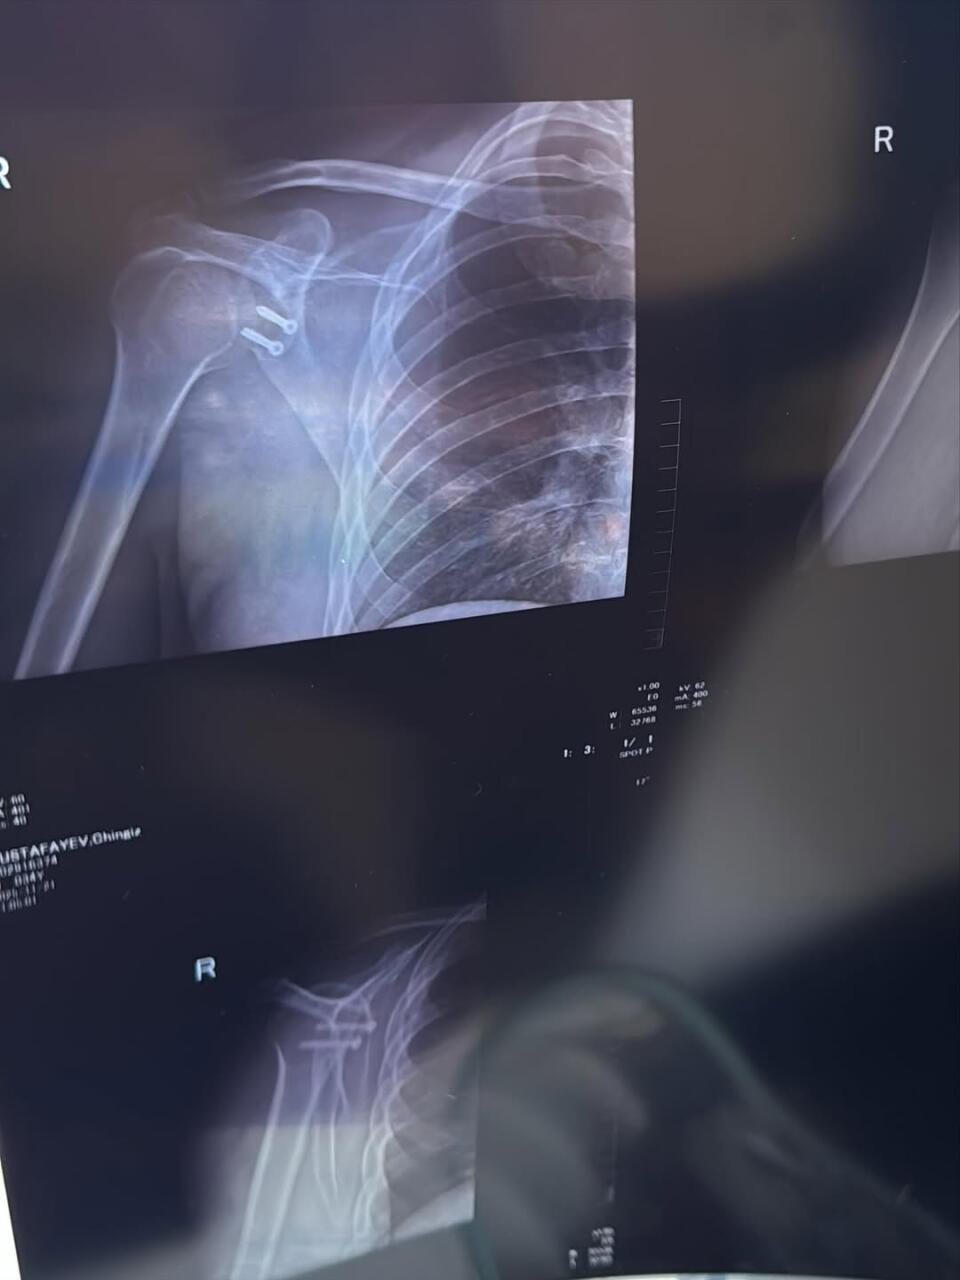

Müğənni Çingiz Mustafayev əməliyyat olunub.

Milli.Az xəbər verir ki, sənətçi xəstəxanadan olan görüntülərini izləyiciləri ilə bölüşüb. O, bildirib ki, çiynində olan problemə görə bıçaq altına yatlıb:

"15 il ərzində çiynim 7 dəfə çıxıb. Hər dəfə eyni ağrı, qorxu, narahatlıq... İdman da, aktiv həyat da tam mümkün olmurdu. Hər dəfə özümə deyirdim: hələ tezdir, bir az da gözləyim bir söznən iş güc və sairə... Amma 2 ay əvvəl sonuncu dəfə çiynim çıxanda anladım ki, artıq bu məsələni həll etməyin vaxtı gəlib. Dünən əməliyyat olundum. İndi uzun bir reabilitasiya dövrü başlayır. Əməliyyat önəmlidir, amma ən çətini sonraki mərhələdir: səbir, intizam və özünü qorumaq".